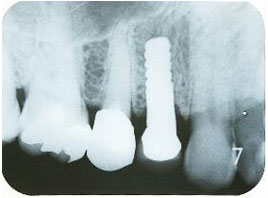

インプラント埋入手術直後のエックス線写真

・20分ほどで埋入終了